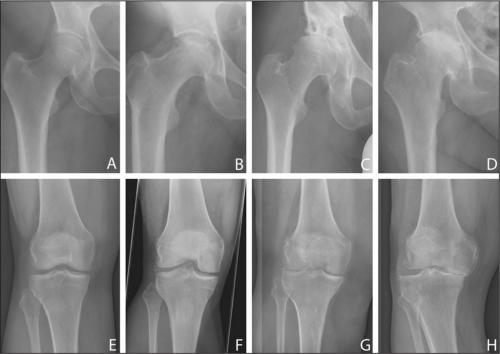

Стадии артроза коленного сустава. Обратите внимание на сужение суставной щели.

Все медикаментозные средства эффективны лишь—, но бессильныи IV. Если в патологию вовлечены не только суставы, но и кости, никакой препарат не поможет. В этом случае избавиться от хронических, трудностей при ходьбе, ограниченной подвижности суставов и других неприятных симптомов можно только с помощью операции.

Все медикаментозные средства эффективны лишь на I—II стадиях артроза, но бессильны на III и IV. Если в патологию вовлечены не только суставы, но и кости, никакой препарат не поможет. В этом случае избавиться от хронических болей в суставах, трудностей при ходьбе, ограниченной подвижности суставов и других неприятных симптомов можно только с помощью операции.